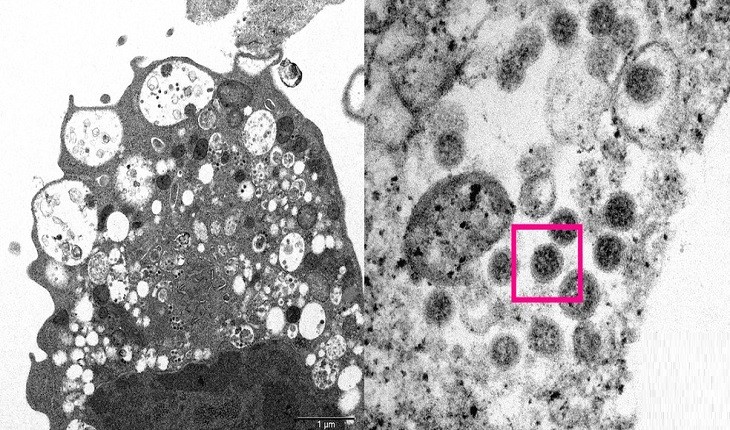

Sintomas clássicos da Covid-19 deixaram de ser predominantes com novas variantes na pandemia.

Estudo analisou infecções pela doença em mais de 8,5 mil lares na Dinamarca entre dezembro e janeiro.